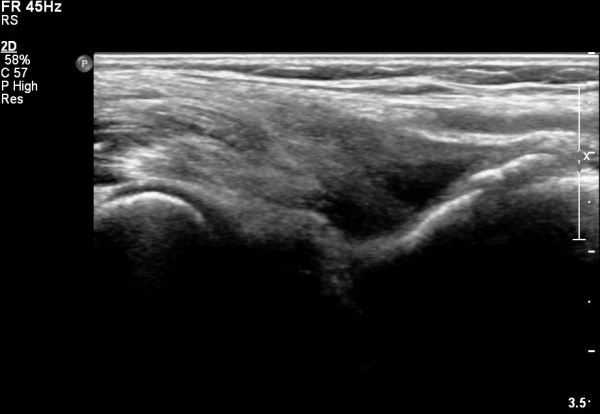

ŽÃËÀÚ¸¦ ¸»´ÜºÎ·Î À̵¿ÇÏ´Ï ¿ä°ñµ¶±â ÀÌµÎ¹Ú±Ù°Ç ÂøºÎ¿¡¼­ °ÏÀÌ Àú¿¡ÄÚ ºÎÁ¾ »óÅ·Π°üÂûµÇ°í(»çÁø 2)

Á¶±Ý´õ ¸»´ÜÀ¸·Î À̵¿ÇÏ´Ï °ÇÀÌ °üÂûµÇÁö ¾ÊÀ½(»çÁø 3).